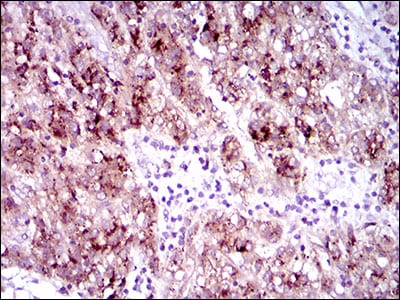

分类: 科研抗体货号: 30507别名: FLK2; STK1; CD135; FLK-2应用: IHC反应种属: Human